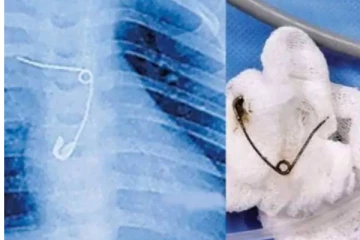

வலியால் துடித்த 8 மாத குழந்தை - சுவாச குழாயில் சிக்கியிருந்த ஊக்கை அகற்றிய மருத்துவர்கள் 4 ஆண்டுகள் முன்